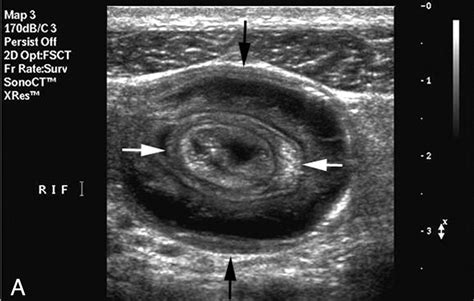

During an ultrasound examination, a transducer is placed on the abdomen. The transducer emits sound waves that penetrate the body and bounce back, creating echoes. These echoes are then converted into images that can be viewed on a monitor. The ultrasound technician or radiologist can identify the characteristic "target" or "doughnut" sign, which is indicative of intussusception. This sign appears as concentric rings of alternating hypoechoic and hyperechoic layers, representing the layers of the intussuscepted bowel.

Interpreting the results of an ultrasound of intussusception requires a trained eye. The characteristic signs of intussusception include:

• Target sign: This appears as concentric rings of alternating hypoechoic and hyperechoic layers, representing the layers of the intussuscepted bowel.

• Pseudo-kidney sign: This sign is seen when the intussuscepted bowel appears as a mass with a hypoechoic center and a hyperechoic periphery, resembling a kidney.

• Crescent-in-doughnut sign: This sign is seen when the intussuscepted bowel appears as a crescent-shaped mass within a doughnut-shaped mass.

These signs, along with the clinical presentation, help healthcare professionals confirm the diagnosis of intussusception.